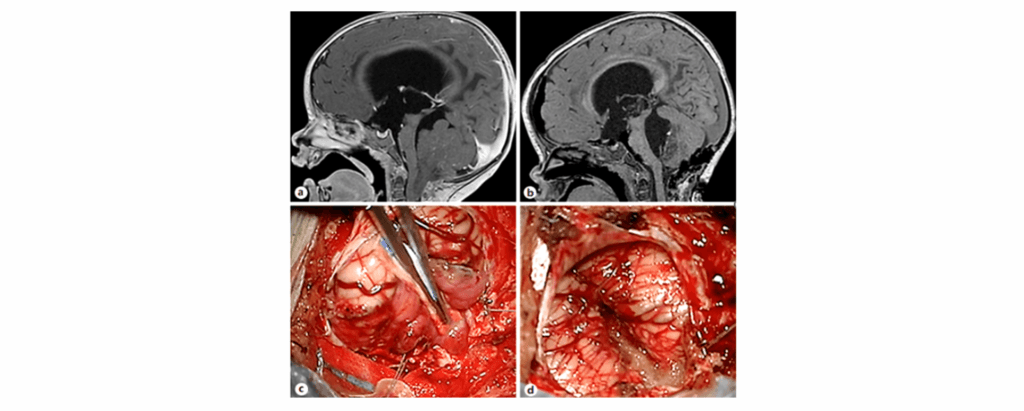

Figure 2. a) Preoperative MRI showing a lesion within the fourth ventricle b) Postoperative T1-weighted MRI confirming gross total resection without haemorrhage; histology: ependymoma (WHO grade II) c) Tumor exposure below the cerebellar haemispheres d) Surgical field filled with thrombin-gelatin haemostatic matrix5

In this study, the thrombin-gelatin haemostatic matrix sealant was found to be a valid and safe tool for strengthening haemostasis in pediatric low-grade posterior fossa surgery.5